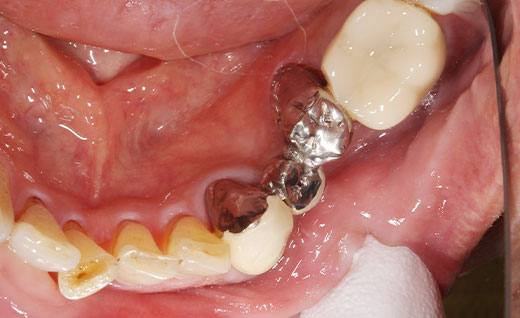

施術中

ジルコニアブリッジの土台を形成しているところです。